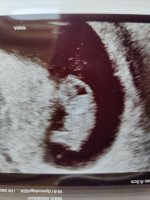

Alt bra med den lille, delte i tråden for ultralydbilder men ville oppdatere her også! En sterk liten sak som vinket og sparket med beina, helt magisk opplevelse![]()